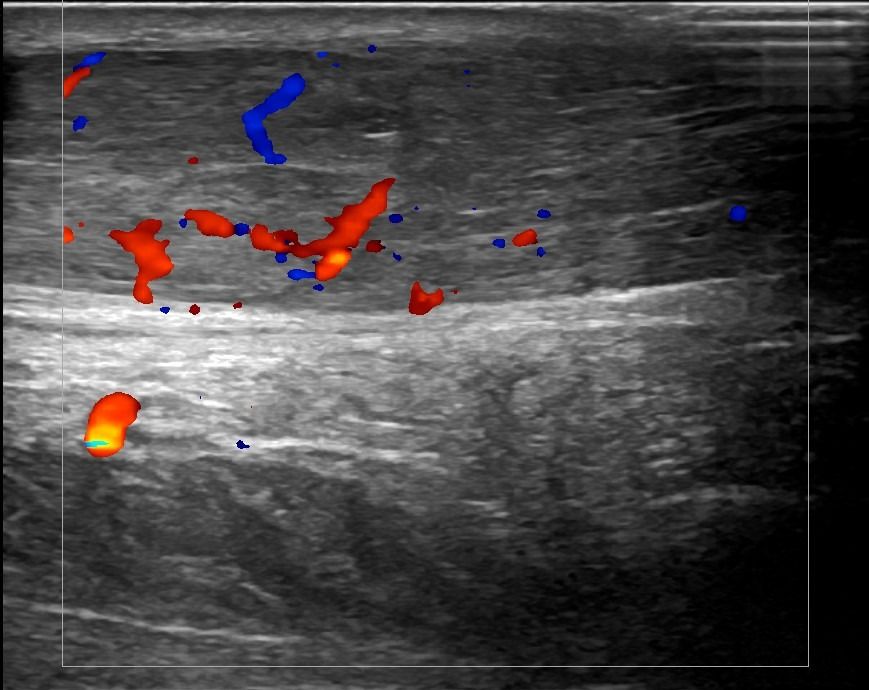

Through Foot and Ankle Ultrasound, a specialized Radiologist can identify issues in the joints, tendons, nerves, and soft tissues of the foot.

Detection of fluid collection, synovitis, and crystal deposits in the joints of the foot may lead to the diagnosis of rheumatic diseases such as:

Foot Ultrasound allows the diagnosis of tendonitis, tenosynovitis, and rupture in the following tendons: